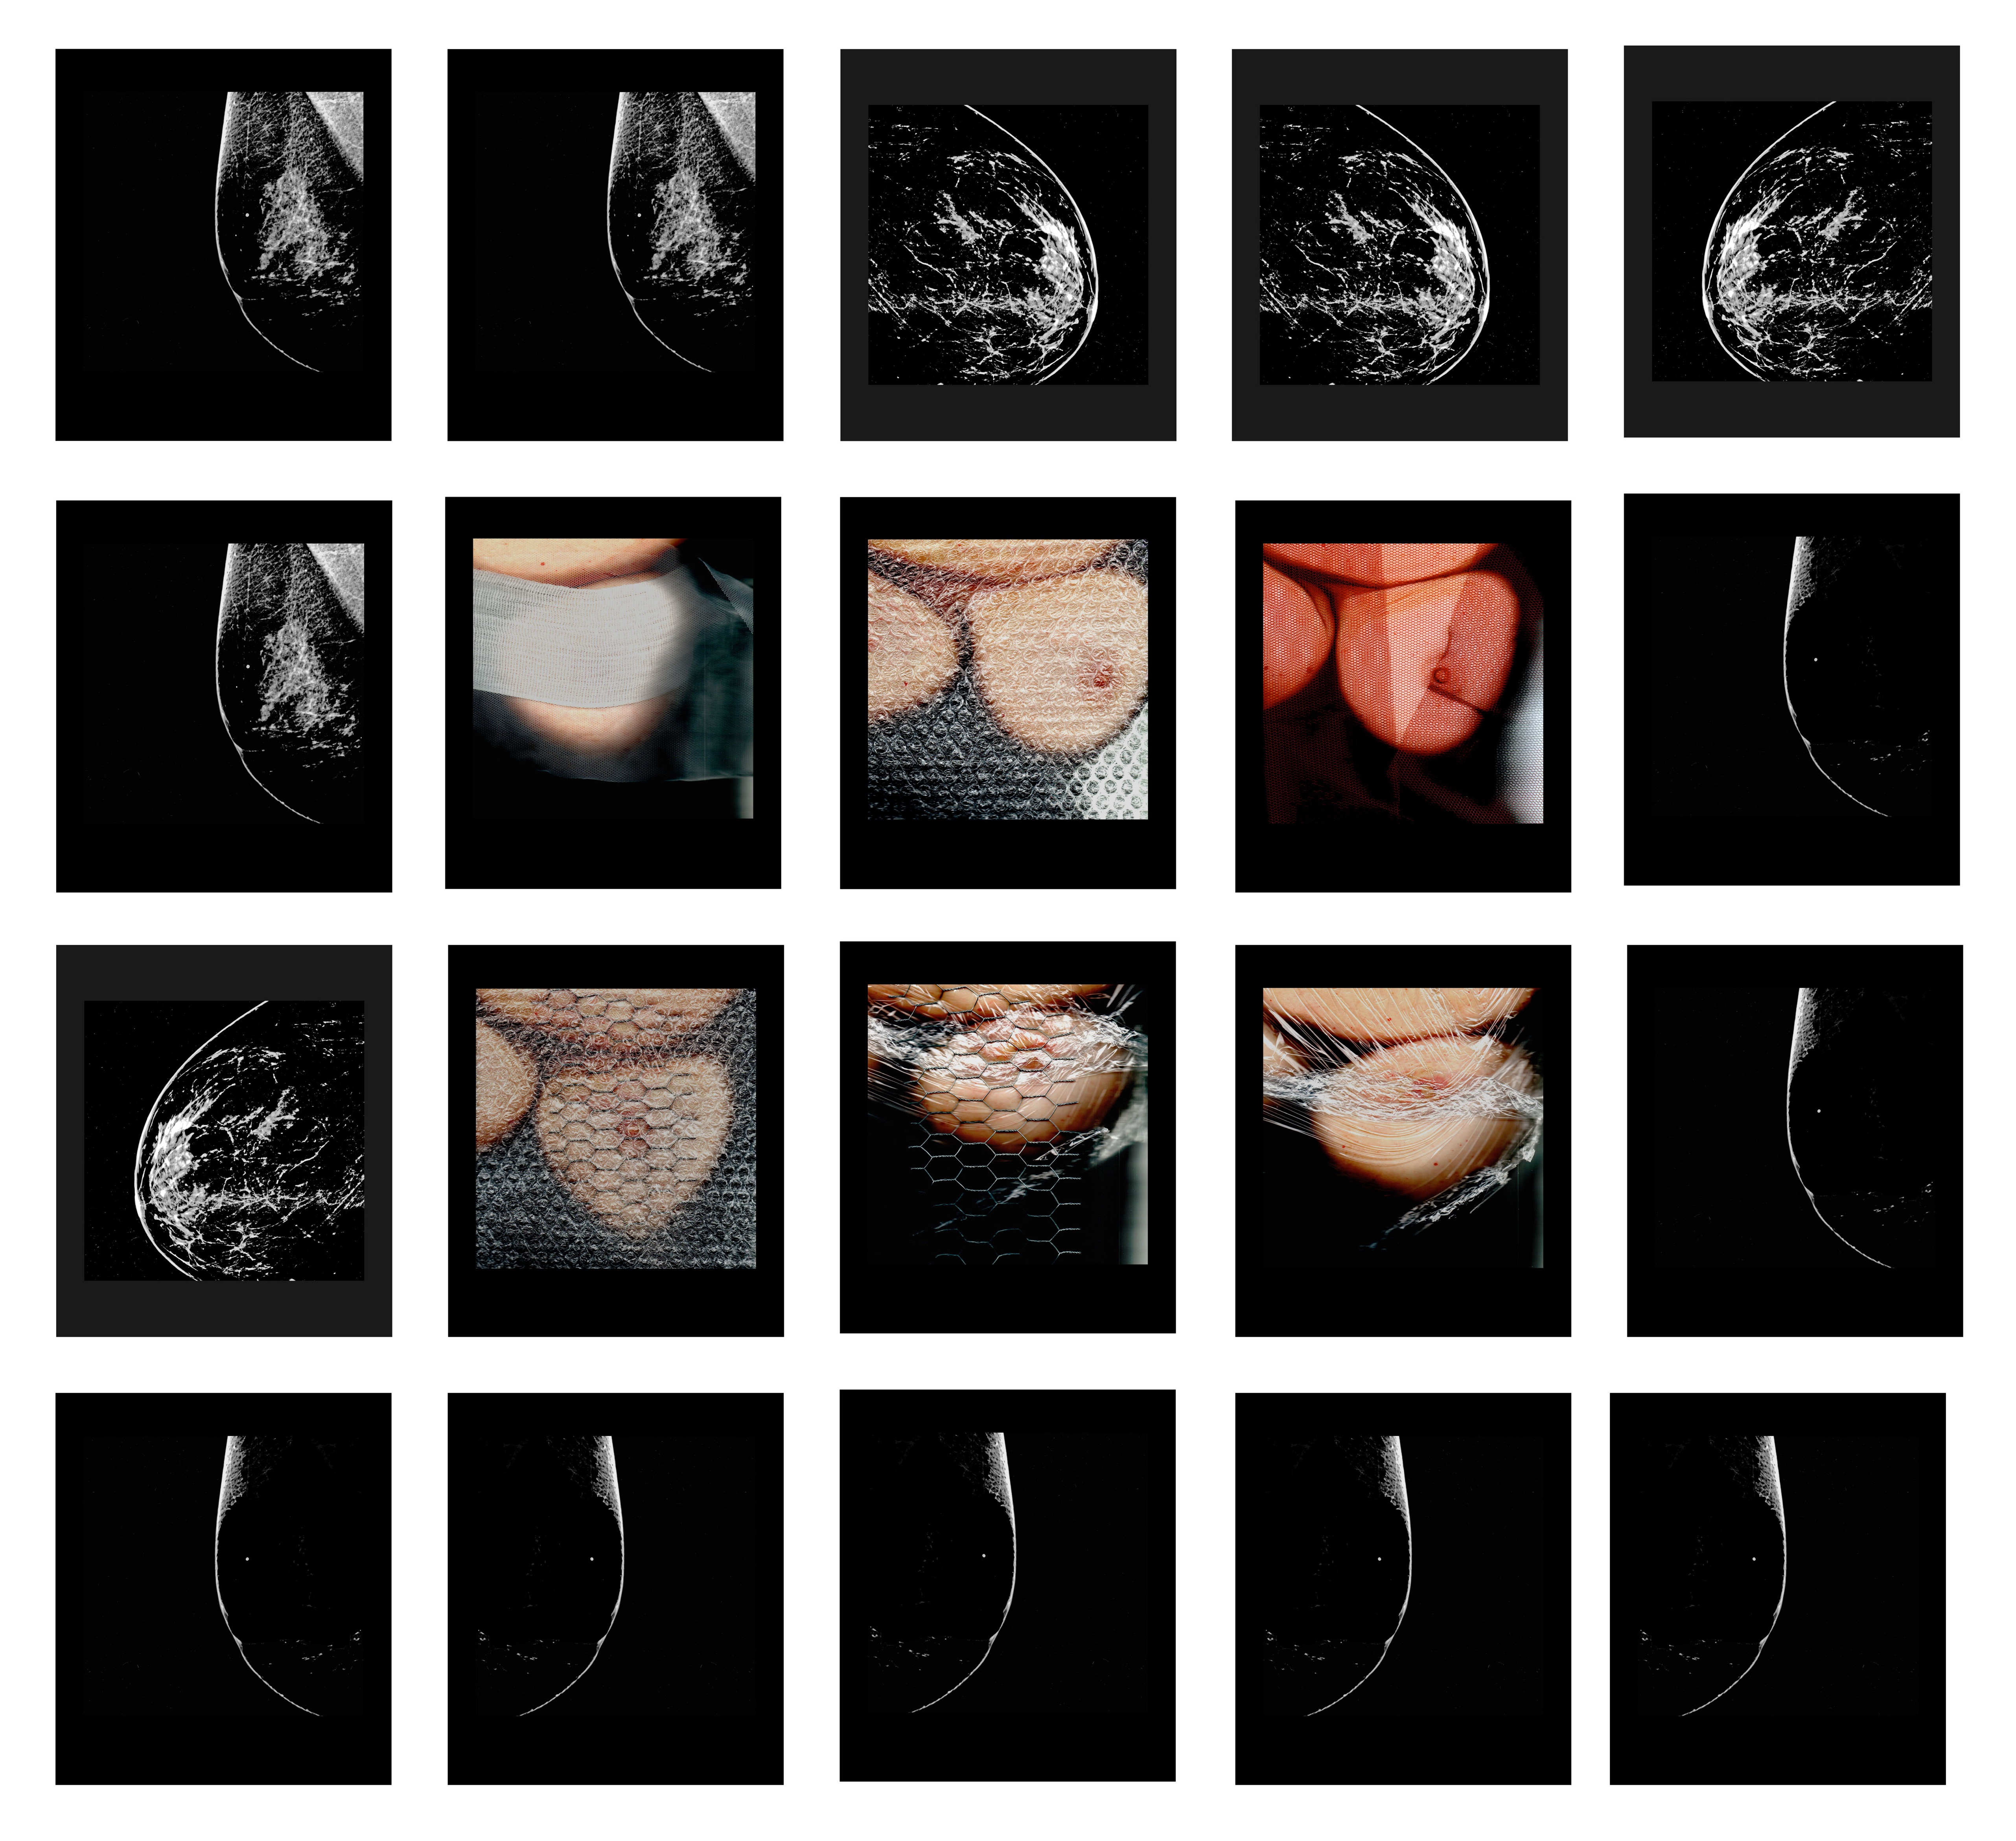

Ομαδική Εικαστική Έκθεση: Μαστογραφίες

Στον εμβληματικό χώρο του Ιδρύματος Εικαστικών Τεχνών Τσιχριτζή, Κασσαβέτη 18, Κηφισιά, η Τέχνη γιορτάζει τον Αγώνα, το Κουράγιο, το Θάρρος, τη Νίκη της Γυναίκας ενάντια στον καρκίνο του μαστού, ενώ παράλληλα αναδεικνύει τους συμβολισμούς του γυναικείου μαστού.

Η ομαδική εικαστική έκθεση ΜΑΣΤΟΓΡΑΦΙΕΣ εγκαινιάζεται το Σάββατο, 27 Σεπτεμβρίου και ώρα 7-10μ.μ. και διαρκεί έως το Σάββατο, 11 Οκτωβρίου 2025.

Εκλεκτοί καλεσμένοι, 11 σύγχρονοι και αξιόλογοι εικαστικοί από Ελλάδα και εξωτερικό που εμπνέονται από τον γυναικείο μαστό, του συμβολισμούς του και τον Οκτώβριο, χρώματος ροζ που είναι διεθνώς αναγνωρισμένος ως μήνας πρόληψης και ενημέρωσης για τον καρκίνο του μαστού.

Κατά τη διάρκεια αυτού του μήνα, πραγματοποιούνται δράσεις ενημέρωσης και ευαισθητοποίησης για την ασθένεια, με σκοπό την έγκαιρη διάγνωση και πρόληψη. Η έγκαιρη διάγνωση μέσω προληπτικών εξετάσεων, όπως η μαστογραφία και το υπερηχογράφημα, αυξάνει σημαντικά τα ποσοστά ίασης.